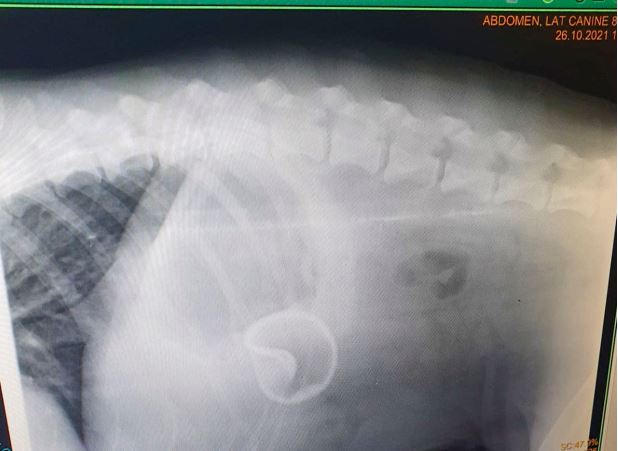

Çekilen röntgende köpeğin karnında bir tenis topu olduğu fark edildi. The Sun gazetesine konuşan Fillery, “Veteriner şoke oldu. 25 senelik meslek hayatında böyle bir olay görmediğini söyledi” dedi.